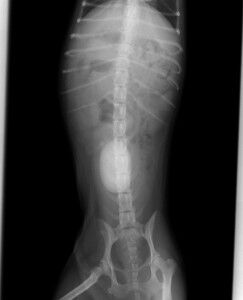

次の日に手術を行いました。取り出した結石が下の写真です。

これまで取り出した結石の中で最大でした。

成分解析した結果、シュウ酸カルシウムという種類の結石でした。

体質的にこの石ができやすい可能性があるので、予防をしないと

またすぐにでも同じような結石が出来る可能性があります。

この結石を予防するためにフードを変えました。3か月経ちましたが、

順調に過ごしています。

慢性の血尿を放っておくと結石が出来て手術をしないといけなくなることがあります。血尿が出たら早めに動物病院を受診しましょう。